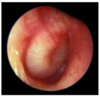

En 27-årig mand har haft kraftige smerter i højre øre siden i går. Kunne ikke sove i nat pga smerterne, trods mange panodil. Har ikke haft øreproblemer tidligere. Objektivt; kraftige smerter når man trækker i øret og trykker på tragus. Vedr otoskopi af højre øre; se foto. Hvad er den mest sandsynlige diagnose?

a. Sekretorisk otitis media

b. Perforatio membrana tympani

c. Akut otitis media

d. Otitis eksterna

e. Cerumen

d. Otitis eksterna

En 3-årig pige har grædt og har taget sig til højre øre. Hun har for tre måneder siden fået målt flade kurver ved tympanometri. Vedr otoskopi af højre øre; se foto. Hvad er den mest sandsynlige diagnose?

a. Kolesteatom

b. Kronisk otitis media

c. Sekretorisk otitis media

d. Akut otitis media

e. Myringitis bullosa

d. Akut otitis media